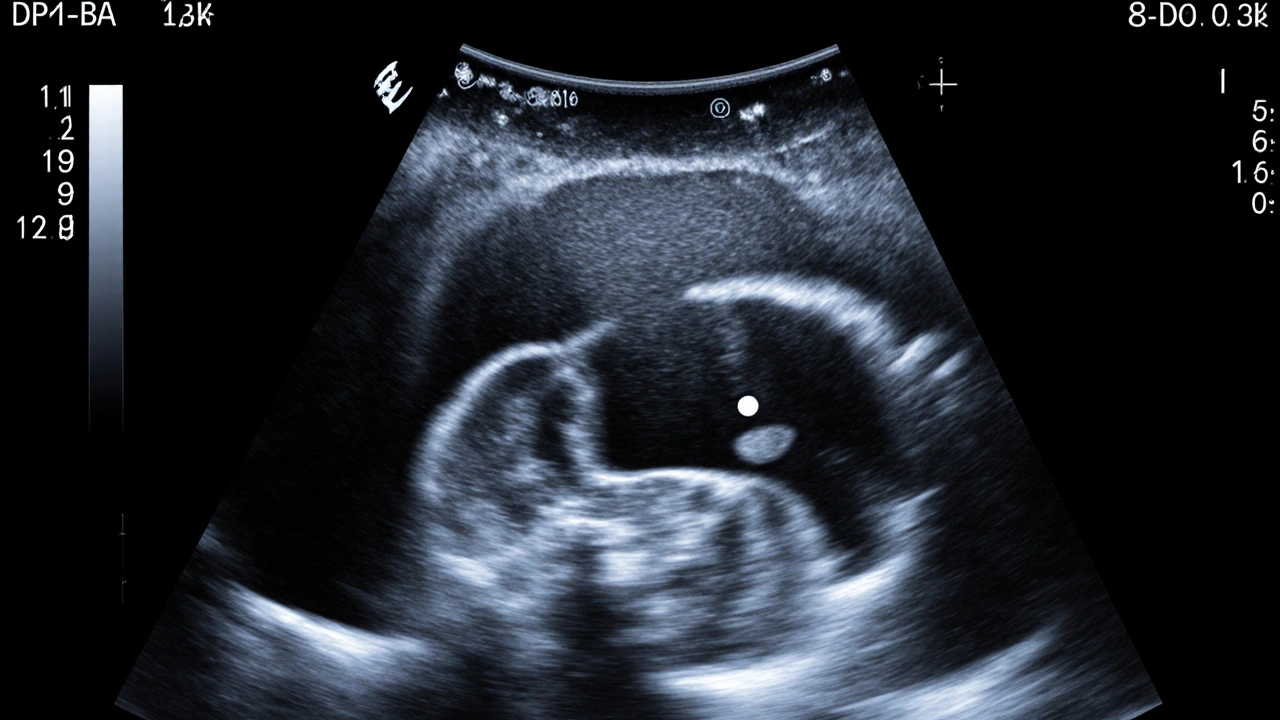

Ultrazvukové snímky z 5. týdne: gestacionální vak, žloutkový vak a malý embryonální bod.

Jaké struktury jsou již viditelné na ultrazvuku?

Na ultrazvuku v pátém týdnu můžete očekávat vidět dva hlavní útvary:

• Gestational sac - první dutina, která obklopuje embryo a naplněná je amniotickým tekutinou.

• Yolk sac - kulovitý útvar, který zásobuje embryo živinami a pomáhá při tvorbě krve.

Samotné embryo (někdy nazývané „bílý teček“) může být až na dobrém přístroji jen stínem. Pokud se vám podaří vidět, bude to první vizuální potvrzení těhotenství po laboratorním testu.